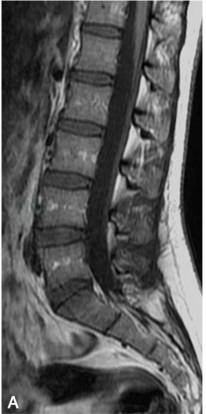

矢状位:显示椎体的连续解剖结构,腰椎呈生理曲度前凸,骶尾椎呈生理性后凸。腰椎椎体呈矩形,椎体边缘骨皮质在T1WI和T2WI上均呈低信号;椎体内随着年龄增长,逐渐由红骨髓向黄骨髓转换,儿童时期主要为红骨髓,T1WI呈低信号,T2WI呈中等信号,随着年龄的增长,椎体内大量脂类或脂肪成分堆积可形成局灶或弥漫性脂肪沉积改变,T1WI呈略高信号,T2WI呈中等信号(图2)。椎体后缘的中间部位有短的条状凹陷,为椎基静脉所致。椎体的附件包括椎弓、椎弓根、椎板、棘突、横突及上、下关节突等,其信号与椎体的信号类似。

图2 正常腰椎MRI图像

A.T1WI;B.T2WI;C.T2WI 脂肪抑制序列椎体松质骨呈中等信号,皮质骨呈低信号,椎体内脂肪沉积呈高信号,脂肪抑制序列呈低信号,脑脊液呈T1为低信号,T2为高信号